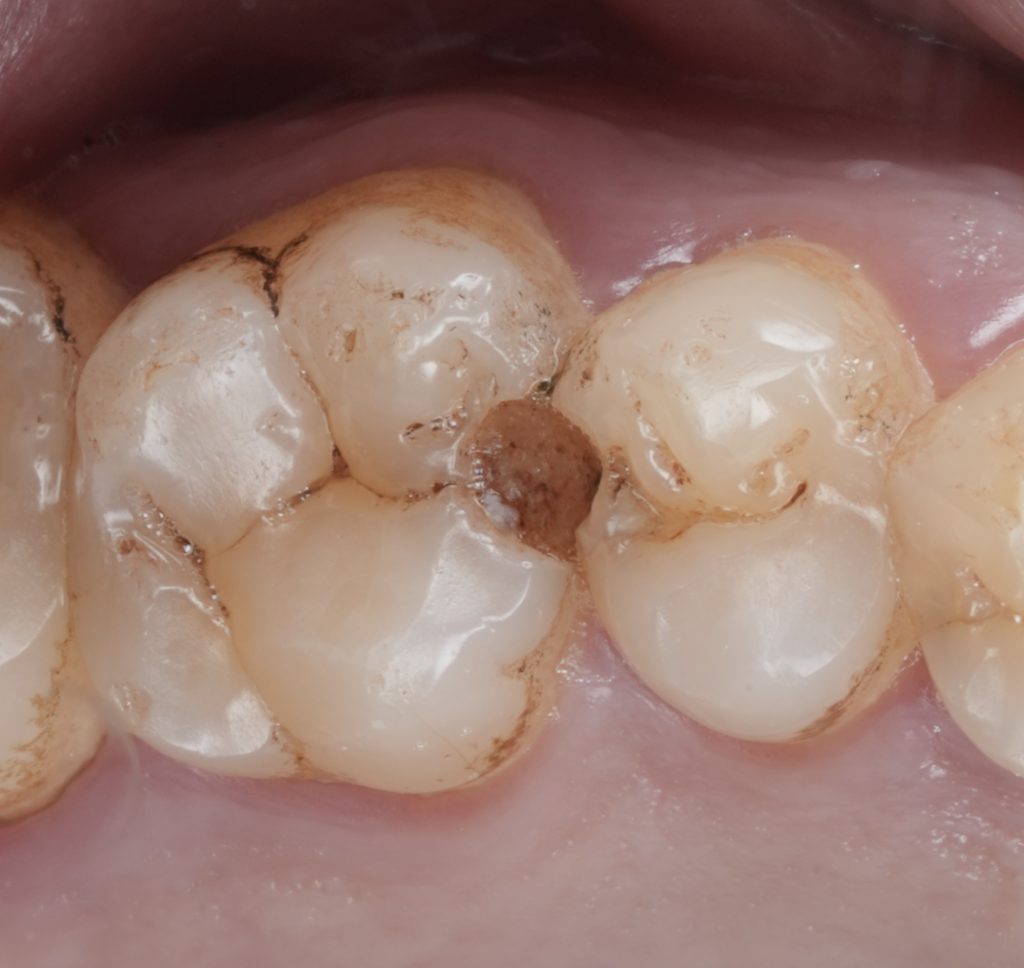

Cavity Preparation and Caries Removal

Caries removal was performed conservatively, focusing on complete elimination of infected dentin while preserving sound tooth structure. The cavity design respected enamel margins and avoided unnecessary extension.

Special attention was given to the gingival margin to ensure clean, accessible bonding surfaces.